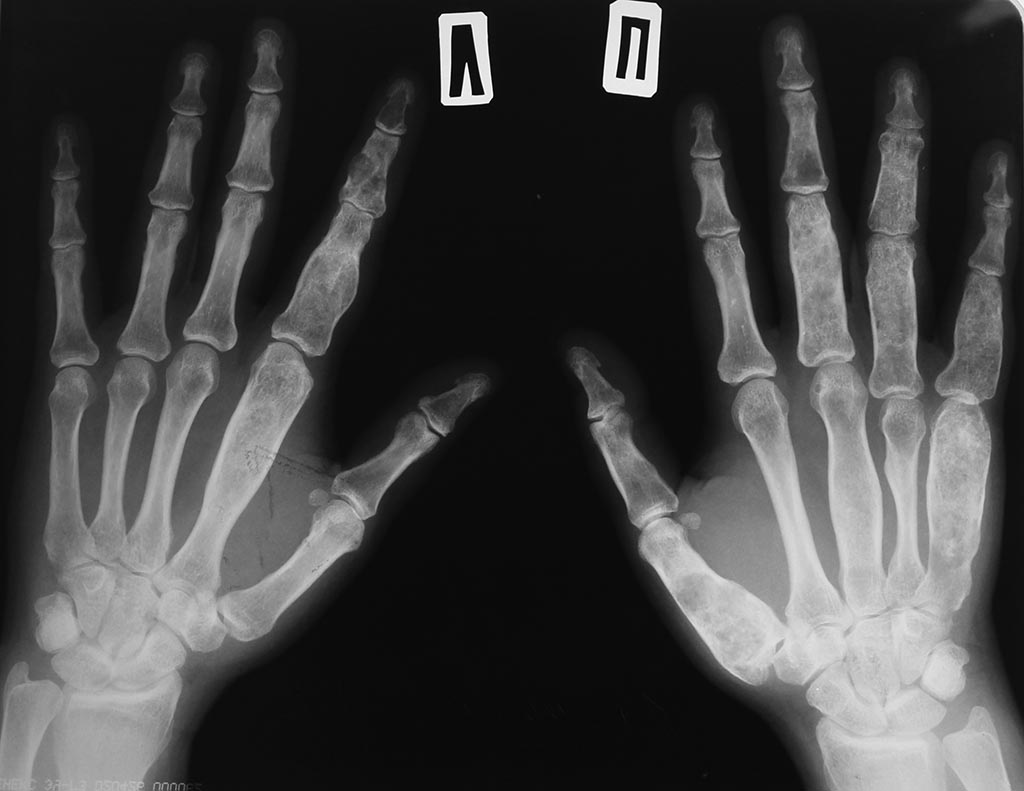

Болеет с 4 летнего возраста, множественные переломы пальцев кисти от незначительных травм.В детстве лечилась в Шумской больнице.После лечилась в ЦИТО у Зацепина остановился процесс после позднего полового созревания и рождения ребенкаА пол года назад возобновился процесс. Был очередной перелом, беспокоят боли.Карту с всеми заключниями ее потеряли в поликлинике.Диагноз точно не знает.Остеодисплазия!Вопрос: что это как правильно назвать? Где почитать?КГ

1.Что мы видим на рентгенограмме? Если говорить максимально просто (а простота - основа логики), то мы видим кисть, кости.

2. Какие кости? Максимально просто - толстые.

3. Итак, мы видим толстые кости кисти.

Вероятно мы имеем дело со склеростеозом.

По Международной классификации первичных опухолей скелета (1998) хрящеобразующие опухоли, доброкаченственные, энхондрома. Леченая неоднократно. Но признаки остались.

То есть на снимках - множественные энхондромы или энхондроматоз?

Дисхондроплазия

А сделайте ради интереса р гр других частей скелета скорее всего там тоже будут изменения. Похоже на болезнь Олье.